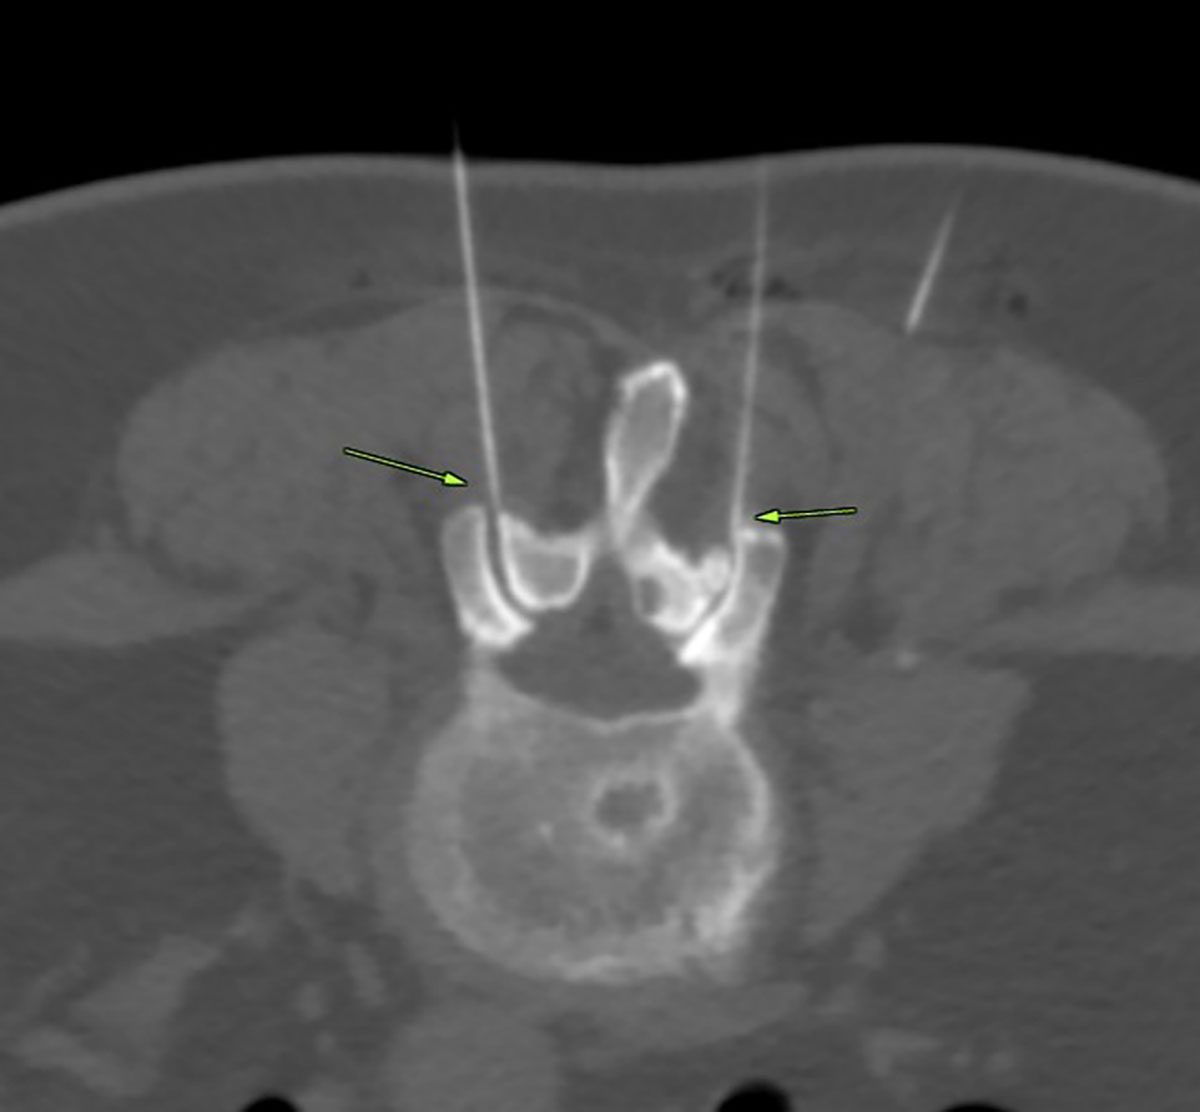

Aufgrund der engen topografischen Beziehung zwischen der knöchernen Wirbelsäule und dem Rückenmark bzw. den austretenden Spinalnerven besteht bei einem Wirbelsäulentrauma immer der Verdacht auf eine gleichzeitige Nervenschädigung mit den damit verbundenen neurologischen Ausfällen. Bei Verletzung von Nerven können zusätzlich Paresen oder Sensibilitätsstörungen auftreten.

Die Hauptgefahr eines Wirbelsäulentraumas liegt in der Schädigung des Rückenmarks durch Quetschung, Einblutung oder Durchtrennen mit Ausbildung einer Querschnittslähmung. Durch Hypotonie, Ischämie oder Ödembildung ist eine sekundäre Rückenmarkschädigung möglich.